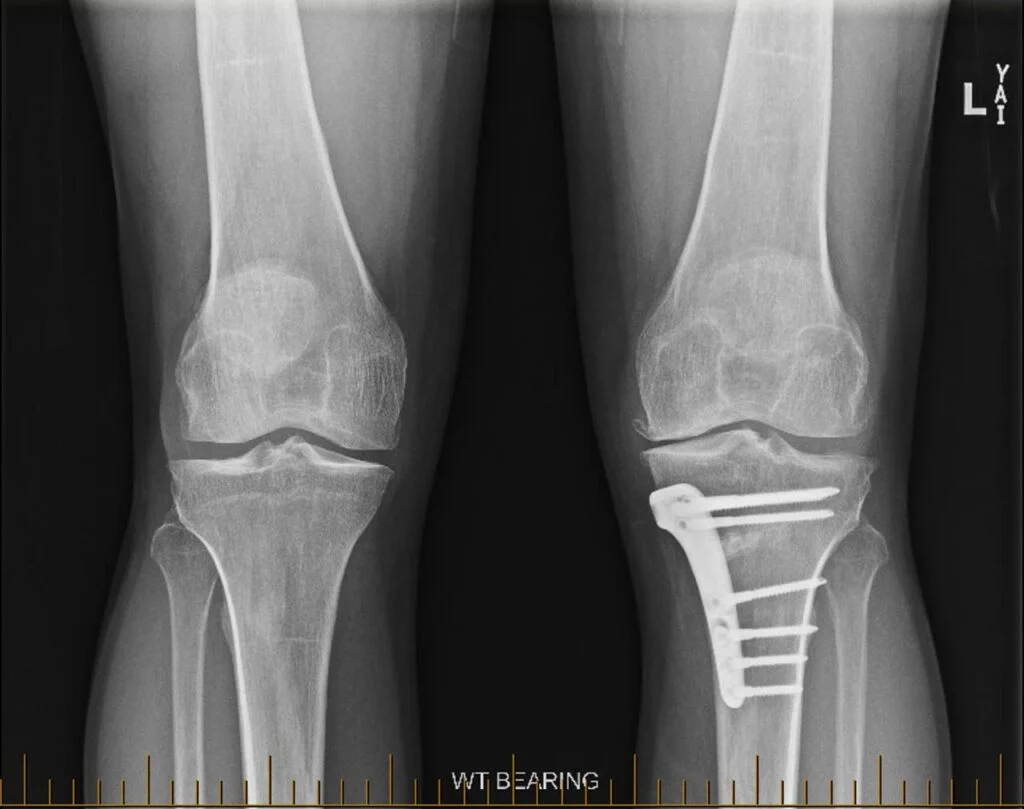

• Partial Knee Replacement Surgery

Partial Knee Replacement